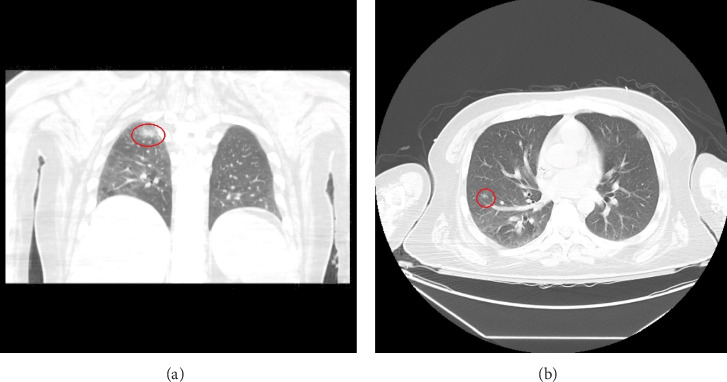

Background: Co-infection with disseminated cryptococcosis and toxoplasma encephalitis is rare but presents significant diagnostic and therapeutic challenges, particularly in severely immunocompromised patients. This case study highlights the complexities involved in managing such dual infections. Case Presentation: We describe a 43-year-old Hispanic male with Stage IV EBV-positive diffuse large B-cell lymphoma and hemophagocytic lymphohistiocytosis who presented with progressive weakness and altered mental status. Initial brain MRI revealed multiple enhancing lesions. Diagnostic tests for cryptococcosis and toxoplasma were inconclusive; however, a positive cryptococcal antigen test, new lung nodules, and potential central nervous system involvement suggested possible disseminated cryptococcosis. Diagnosis of cryptococcal meningoencephalitis could not be confirmed due to negative CSF cultures. Management and Outcome: Despite initiating treatment with amphotericin B and flucytosine for suspected cryptococcosis, the patient's condition did not improve. Initial Karius and CSF PCR tests for Toxoplasma were negative. A subsequent brain biopsy, however, confirmed toxoplasmic encephalitis. Treatment was adjusted to intravenous Trimethoprim/Sulfamethoxazole for toxoplasmosis, with continued fluconazole for cryptococcosis. The patient exhibited significant clinical improvement with this revised therapy. Conclusion: Diagnosing concurrent cryptococcal and toxoplasma infections is challenging due to overlapping clinical symptoms and variability in test sensitivities. This case underscores the need for a comprehensive diagnostic approach and the critical role of brain biopsy when other diagnostic methods, such as Karius testing and CSF PCR, are inconclusive. Prompt empirical treatment based on clinical suspicion, with subsequent treatment adjustments guided by clinical response and follow-up assessments, is essential for effective management.

Abstract Image